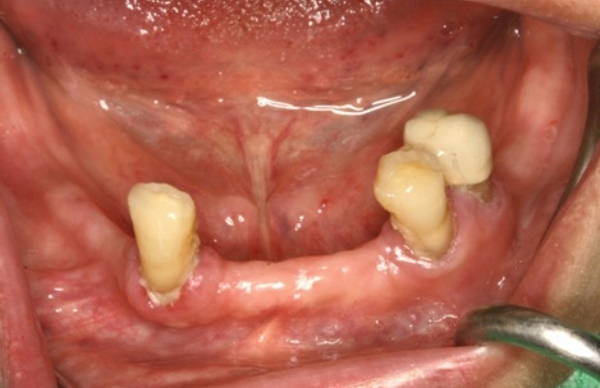

牙齒動牙須拔除

銀髮族植牙